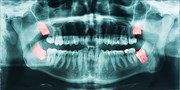

The first step is to assess the extent of the damage. Not all dental injuries are the same, and understanding the severity of the issue can help you make informed decisions about how to proceed.

A more substantial chip may expose the sensitive dentin layer, leading to heightened sensitivity or pain. Assess the size of the chip and any potential jagged edges.

Severe Break

In the case of a severe break, where a significant portion of the tooth is missing, you may experience severe pain and bleeding. Immediate dental care is essential in this situation.

Dental injuries require professional attention, as they can worsen if left untreated. Your dentist will assess the damage and recommend the appropriate treatment, which may include:

- Bonding: For minor chips, your dentist can use tooth-coloured resin to repair the damaged area, restoring its appearance and function.

- Dental Crowns: Severe chips or breaks may require a dental crown covering and protecting the damaged tooth.

- Root Canal: If the tooth's pulp is exposed or damaged, a root canal may be necessary to remove infected or damaged tissue.

- Extraction: Extraction may be the only option in extreme cases where the tooth cannot be saved.